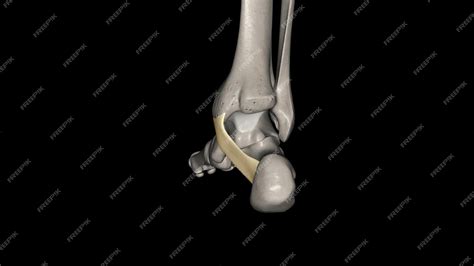

The flexor retinaculum is a thick, fibrous band that stretches from the medial malleolus—the bony prominence on the inside of your ankle—to the medial tubercle of the calcaneus, or heel bone. Its primary purpose is to act as a ligamentous sheath, binding down the tendons of the deep muscles of the posterior compartment of the leg.

By holding these tendons close to the ankle bone, the flexor retinaculum foot structure prevents "bowstringing" during movement. When the muscles in your calf contract to point your toes downward or flex your foot, these tendons would naturally pull away from the bone if not for the restraining force of the retinaculum. This allows for efficient transfer of force, enabling smooth walking, running, and jumping.